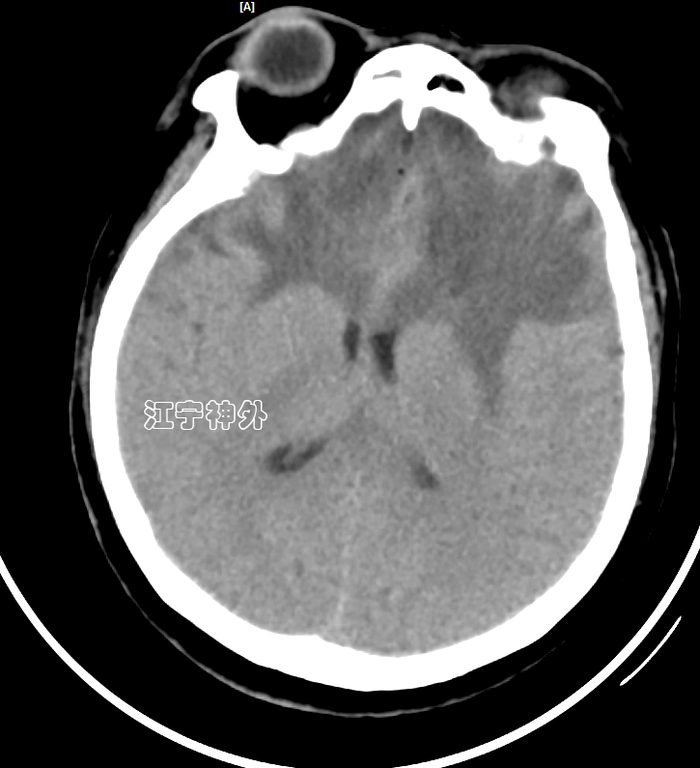

术后第二天复查CT,显示术野无明显出血,脑组织肿胀明显。